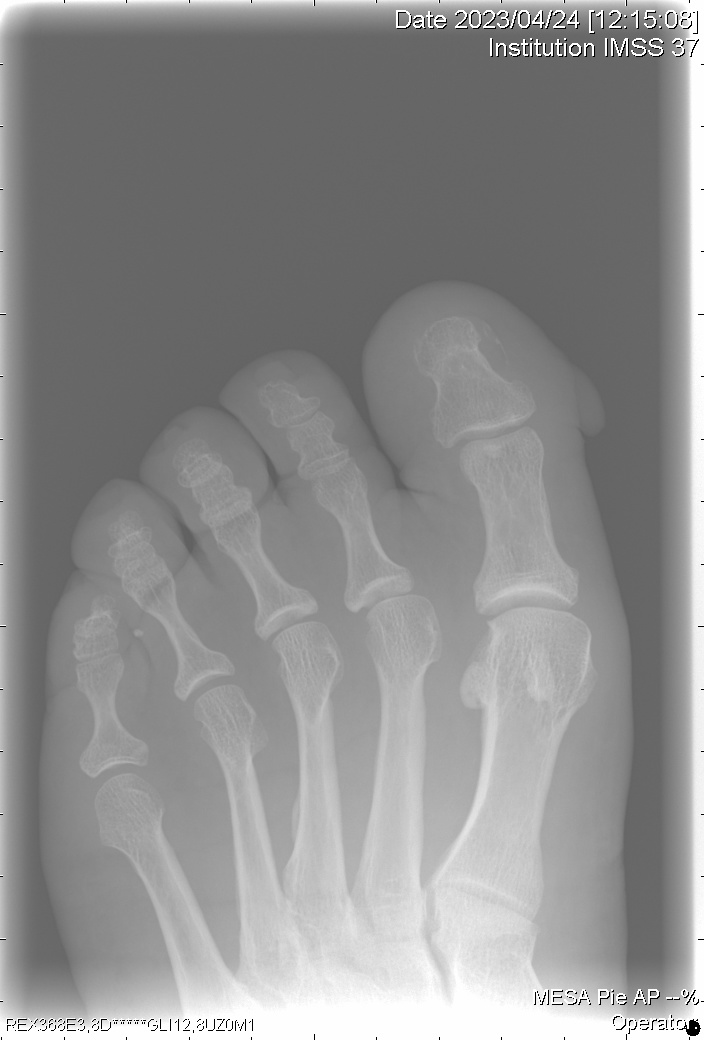

Examen clínico: Evaluación de la forma, tamaño y características de la lesión.

Dermatoscopia: Para observar patrones vasculares y estructurales.

Biopsia: En casos dudosos, para confirmar la ausencia de células malignas.